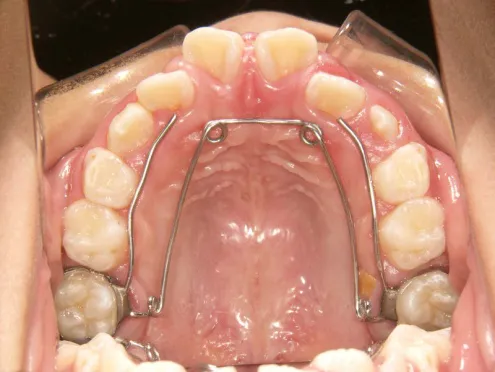

治療スタート:8y2m QH・BHで拡大、前歯の並び替えスタート

QH